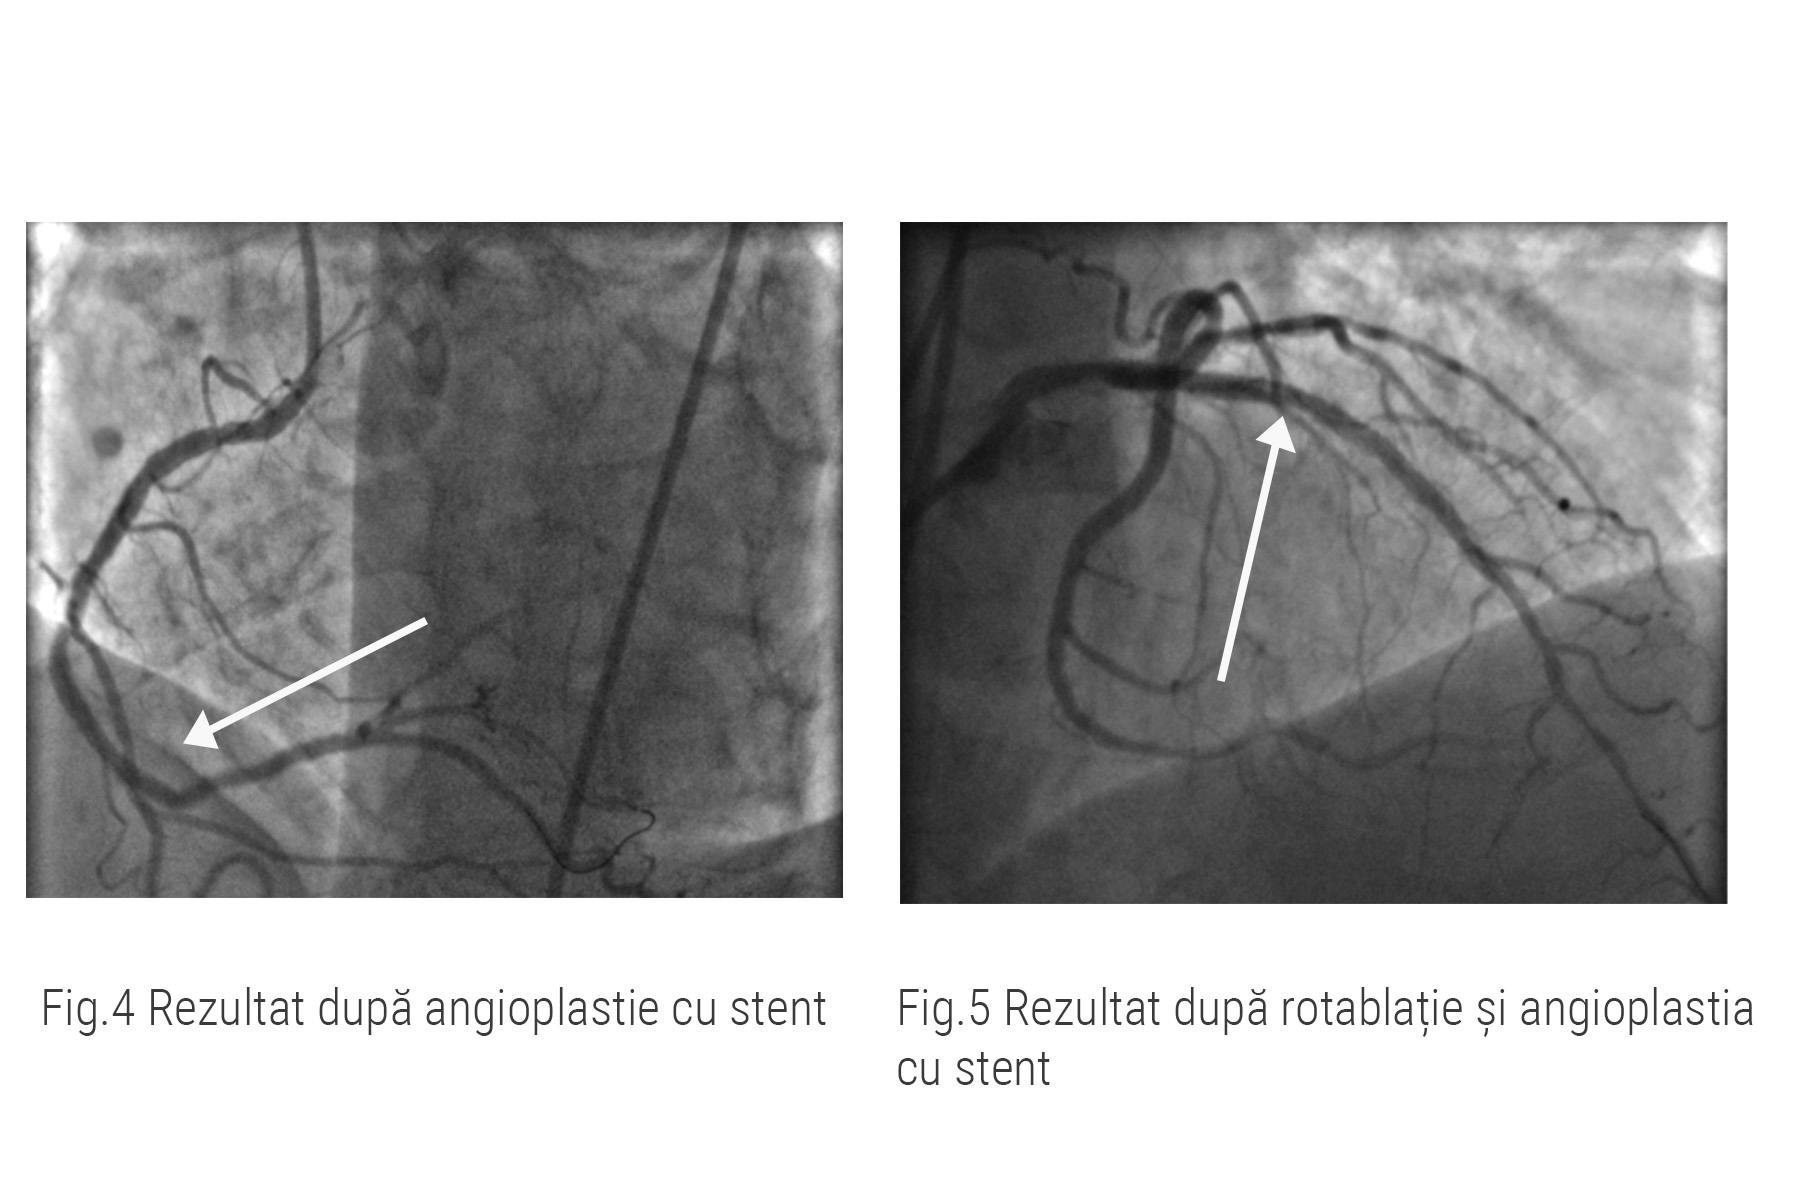

Pentru a reda circulația sângelui în artera coronară dreaptă, doctorul Nicolae Cârstea a efectuat dilatarea cu balon și ulterior, implantarea de stent. Rezultatul se poate vedea în imaginile de mai jos.

Rezultatul procedurii prezentate astăzi este un succes ceea ce înseamnă că pacientul nostru este în afara pericolului de a suferit un infarct miocardic(fig.4, fig.5).